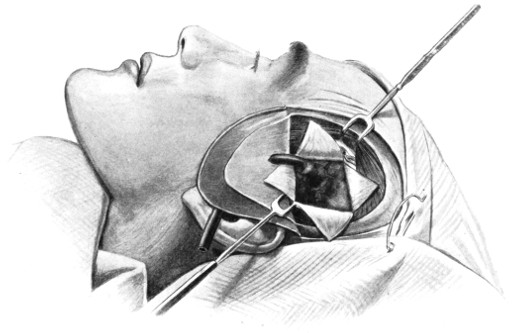

Fig. 18. Second Stage in the Formation of an Osteoplastic Flap. The bone-flap turned down and the dura mater exposed.

The dura is now separated from the bone along the line of the two vertical incisions, and the visceral blade of de Vilbiss’s forceps insinuated beneath the bone, starting at one trephine-hole and working downwards to the lower limit of the incision. It is essential that the operator should be satisfied with the ‘morcellement’ of small portions of bone at each bite of the instrument. At the lower end of each[28] of the vertical incisions the forceps is directed inwards for 1⁄4 to 1⁄2 inch so as to weaken the base of the flap.

To lift up the osteoplastic flap, a stout elevator or spatula is introduced beneath the bone at its upper part, leverage applied, and, as soon as sufficient elevation has been attained, the dura mater carefully separated from the whole of the under aspect of the flap. The flap is then grasped at its upper part with both hands and, with a quick but forcible jerk, broken across at its base, the assistant at the same time aiding the correct linear fracture of the bone by a flat spatula applied to the outer aspect of the base of the flap. Insomuch as the flap is most usually framed in the parieto-temporal region—for the exposure of the motor area—the base of the flap, being formed from the squamous portion of the temporal bone, is comparatively weak. Fracture is then readily obtained. Under other circumstances the base may be sufficiently weakened by the application of the de Vilbiss forceps or by the use of the Gigli saw.